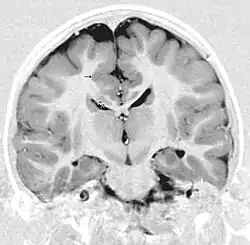

MRT eines Kindes mit Krampfanfällen. Coronare Darstellung mit verdickter und ungeordneter Großhirnrinde bds im Gyrus cinguli und Gyrus frontalis superior (Pfeile). Heterotopien (Doppelpfeile)

Die Diagnose erfolgt bildgebend mittels Magnetresonanztomographie, bei der Unregelmäßigkeiten der Hirnrindenoberfläche, am Übergang zur grauen Substanz sowie eine Verdickung der Hirnrinde nachgewiesen werden können.[2][3][9]